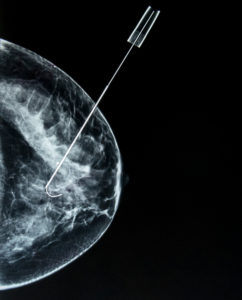

The most common practice for lumpectomies presently utilizes a localization procedure performed on the day of surgery. This localization is done to help the surgeon find exactly where to remove abnormal tissue or cancer that cannot be palpated. Traditionally an eight-inch wire with a hook is inserted into the breast and placed next to the target. Once the wire is placed, a mammogram or ultrasound is done to confirm placement.

One of the concerns with wire localization is the potential for movement. The placed wire protrudes from the breast of the patient once positioned. While patients go directly to surgery after the wire has been set, radiology and surgery are in two separate locations.